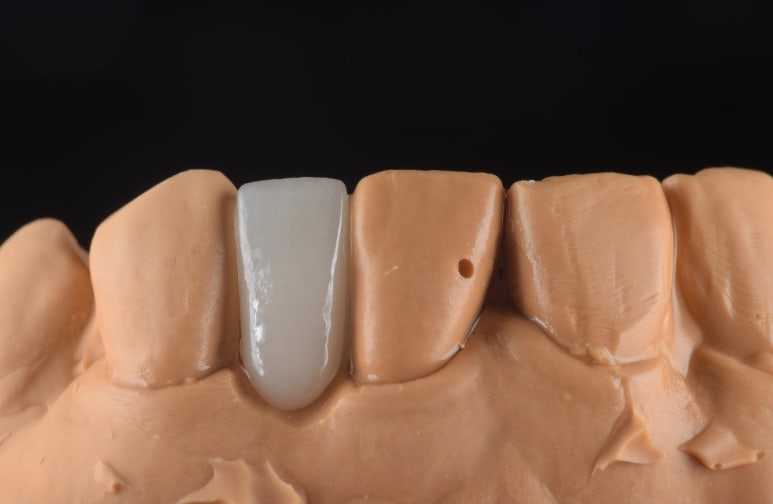

2) 정밀한 기공 제작

기공소장님과 긴밀히 소통하여

환자분의 치아 색상과 투명도를

자연치아와 유사하게 재현한

보철물을 의뢰했고, 정성스럽게 제작된

보철물을 확인했습니다.